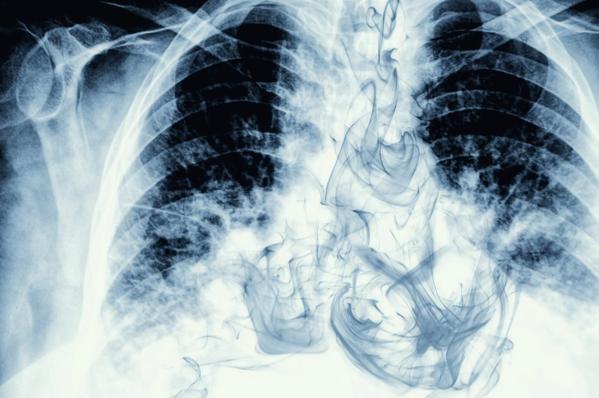

Smoke visible on chest X-ray image

As these illnesses come into focus, physicians are quickly trying to learn more, as still little is known of the long-term effects of vaping. Along with these serious cases, anecdotal evidence reveals some of their impact mirrors that of traditional cigarettes. Recently, a young woman came to us at Cleveland Clinic reporting breathing difficulties. A CT scan showed inflammation in both lungs, but no signs of cancer or other sicknesses that typically cause this kind of inflammation. Only when the woman – in her twenties – explained that she had just started vaping two months ago did doctors ascertain the source of her problem.